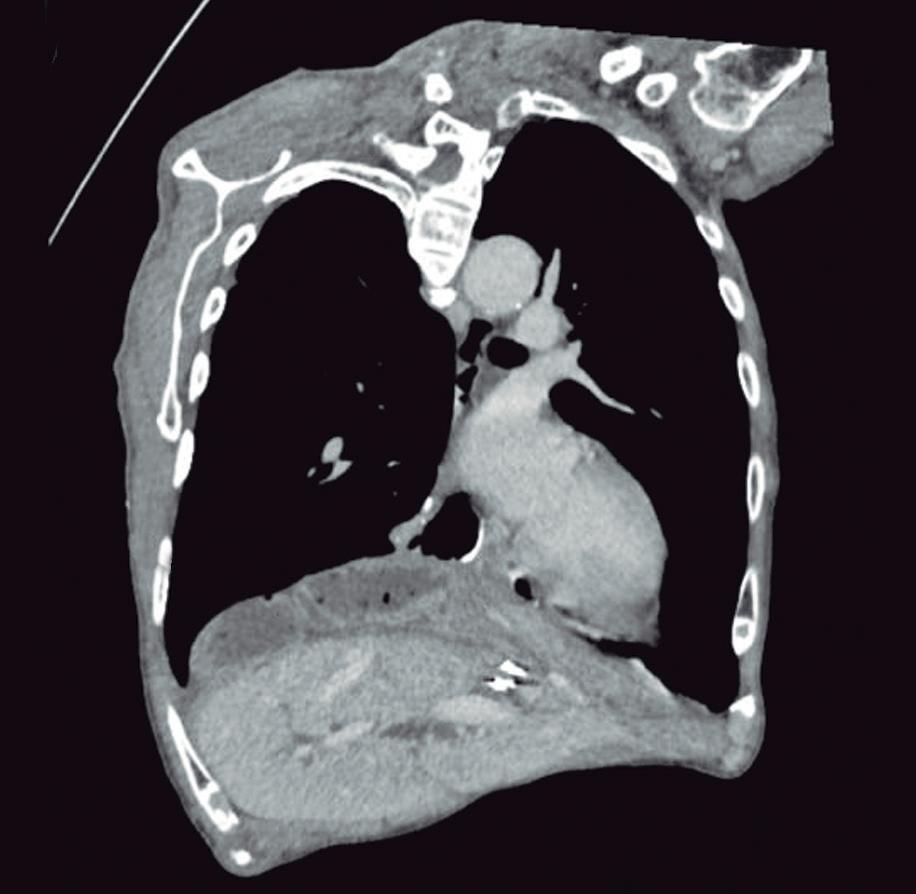

Masa oculta: reto diagnóstico en una adolescente con dolor abdominal agudo

Ivonne Loaiza Pacheco, Diana Marcela Rodríguez De la Hoz, Manuela Laguna Kirof, Nebil Larrañaga, Eugenia Orozco

Hidden Mass: Diagnostic Challenge in a Teenager with Acute Abdominal Pain